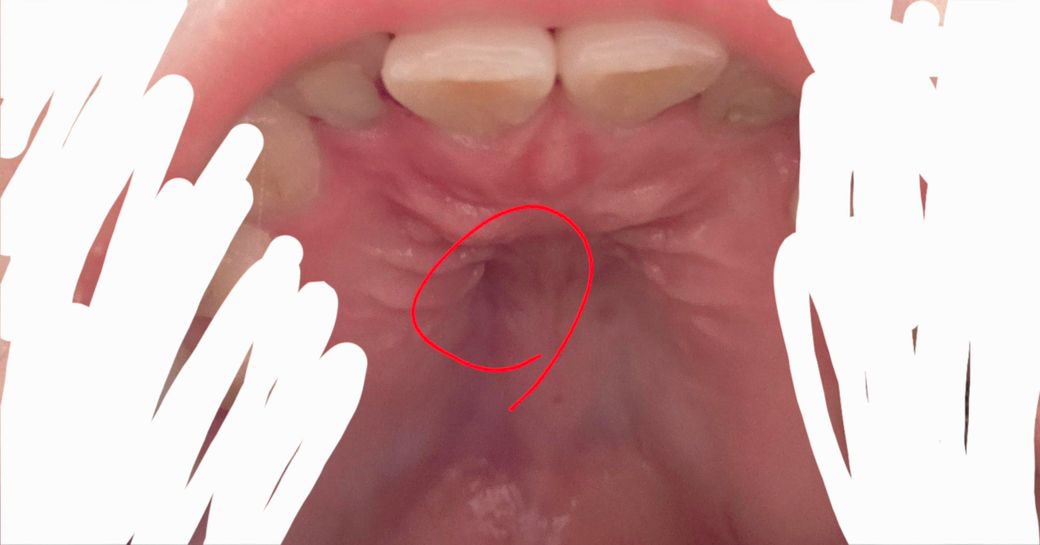

입천장부근은 저쯤이에요

꺾이는 부분부터 근방이 아픕니다 ㅜㅜ

잇몸 주변부의 염증으로 저 곳이 아프지는 않고 뿌리 끝이 위치한 곳이라 저 부위가 붓고 아프다면 치아의 신경에 염증이 생겨서 뿌리 끝쪽에 통증과 부종이 동반되었을 수 있습니다. 일단 오늘 첫 진료 하셨고 다음에도 다시한번 내원하라고 하셨으니 약 복용 잘하시고 치료 마무리 한 후에 재평가 해보셔야겠습니다.

사진에 표시한곳이 아프다면 염증떄문이라기 보다는 입천장이 음식이나 다른거에 자극을 받아서 상처가 생겨서 그럴수도 있습니다. 그리고 구내염일 가능성도 있습니다.